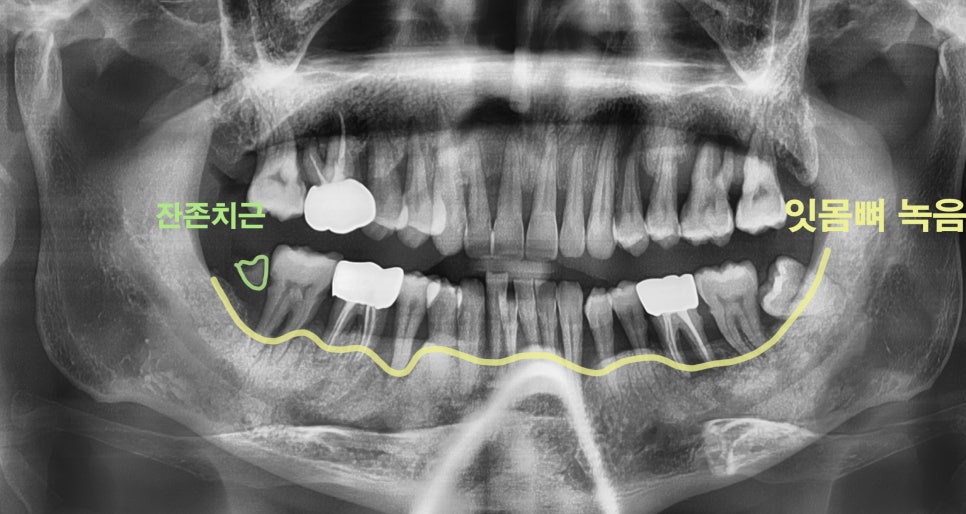

파노라마 사진을 보면

치아를 감싸고 있어야 될 잇몸뼈가

아래쪽으로 쭈–욱 내려간 것을 볼 수 있으며

잔존 치근/ 뿌리끝 염증으로

전체적으로 치아 상태가 좋지 못했습니다.